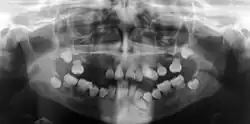

Die Dentindysplasie (DD) ist eine seltene angeborene Störung der Dentinbildung. Bei dieser Zahnentwicklungsstörung sieht das Dentin der Zahnkronen normal aus, die Zahnpulpa ist verödet, die Zahnwurzeln sind nicht normal ausgebildet. Es besteht eine Neigung zu knöchernen Veränderungen der Alveolarknochen.[1]

Das initial gebildete Dentin ist normal, beim Typ I findet sich in der obliterierten Pulpa atypische knollenartige Hartsubstanz. Bei bleibenden Zähnen kann ein halbmondförmiger Rest der Pulpa auf Höhe der Schmelz-Zement-Grenze bestehen bleiben.[2] Beim Typ II ist die Pulpa distelartig und nicht vollständig obliteriert. Die Wurzel ist normal lang, aber dünner.[2]

Typ I hat Zähne ohne oder mit spitzen konischen Wurzeln. Es kommt häufig zu vorzeitigem Zahnverlust.

Typ II hat Zähne mit normalen Wurzeln, einer bernsteinartigen Verfärbung der Milchzähne. Die bleibenden Zähne sind nicht oder nur gering verändert. Es treten vermehrt Knochenläsionen der Alveolarfortsätze auf.[1]

Die Diagnose ergibt sich aus der zahnärztlichen Untersuchung einschließlich der Orthopantomographie.[10]